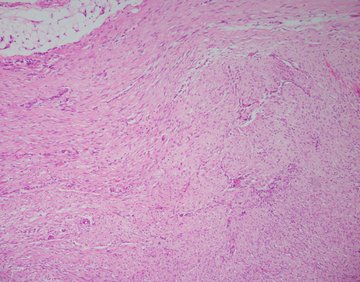

A 34-year-old male presents to the emergency department with abdominal pain. Imaging shows a circumfrential mass causing obstruction of the small bowel. Sections of the mass (H&E shown below) show a mesenteric based spindle cell proliferation with long sweeping fascicles, small blood vessels, bland cytology, no mitoses or necrosis. Immunohistochemical stain for beta catenin shows nuclear positivity in the lesional cells (IHC shown below), and they are negative for desmin, S100, CD117, and SOX10.

Grossly, the lesions are firm with tan-white cut surfaces, often located in the mesentery of small bowel or colon. Histologic sections usually show a low-grade spindle cell proliferation in long sweeping fascicles. Small blood vessels often show perivascular edema. Desmoid fibromatosis should be included in the differential for a spindle cell lesion in the gastrointestinal tract. Other differential diagnoses includes gastrointestinal stromal tumor (GIST), leiomyoma, inflammatory myofibroblastic tumor (IMT), schwannoma, or nodular fasciitis.